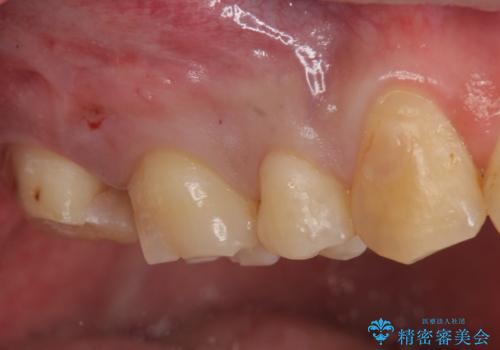

- 一番奥の銀の詰め物を白くしたいとのことで来院。

セラミックの詰め物のやりかえだと範囲が多く、割れてしまうリスクがあります。

そのため、割れるリスクが少ない詰め物ではなく、被せ物による治療(ジルコニアクラウン)を行いました。

また、隣の歯も白い樹脂の下が虫歯になっており、セラミックの詰め物(e-maxインレー)による修復をしました。